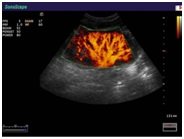

В Медицинском центре «АКВА МЕД МАРИН» проводится УЗИ-диагностика на новейшем ультразвуковом диагностическом сканере Экспертного класса SonoScape S40Exp, в том числе и УЗИ детям с применением специальных детских датчиков. Цветной допплер помогает точной диагностике патологии сосудов и сердца у детей.

Компания SonoScape уделила особое внимание допплеровским режимам и является экспертом в своем классе, что позволяет с легкостью, но в то же время с уникальной точностью проводить исследования с постановкой наиболее точного диагноза.

Ультразвуковые исследования, доплеровское сканирование сосудов в Медицинском центре «АКВА МЕД МАРИН» выполняется при помощи аппарата SonoScape S40Exp (экспертного класса, который оснащен множеством новейших функций, многократно улучшающих качество и информативность УЗИ-исследования).